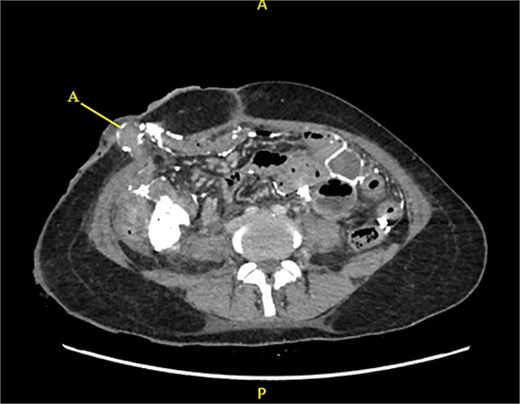

Contrast-enhanced CT of the abdomen and pelvis revealed extensive barium extravasation outlining the peritoneal cavity, accompanied by pneumoperitoneum (Fig. 3). Two barium-outlined, walled-off intra-abdominal collections were identified: one located anterior to the lower pole of the left kidney and the other in the pelvis, anterior to the rectum (Figs 4 and 5). Due to significant barium-related imaging artifacts, the precise site of bowel perforation was not identified. A diagnosis of peritonitis secondary to barium spillage was established, with associated intra-abdominal collections.

Barium-lined intra-abdominal collection (A) anterior to the left kidney (B).